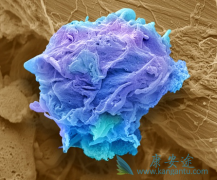

PD-1\PD-L1免疫检测点抑制剂 ,治疗癌症的重磅炸弹!它被美国权威杂志《科学》评为2013年十大科技进展首席地位,是继手术和放化疗及靶向治疗中的又一大利器,是癌症治疗领域一颗璀璨的明星,在多种癌症治疗中脱颖而出。 如果说癌症免疫治疗是精美绝 ...

近几年来,以 PD-1抑制剂 为代表的免疫药物自上市以来一路高歌猛进,捷报频传,各个媒体争相报道。关于免疫治疗的信息更是铺天盖地,让人眼花缭乱。但对患者而言,信息太多反而带来了新的烦恼。如此多的信息,哪些是患者真正需要的?哪些是真哪些是假? ...

免疫检查点抑制剂( PD-1抗体 类药物)的应用引领了肿瘤治疗的重大变革。毫无疑问,PD-1/PD-L1 抗体药物是这两年,肿瘤治疗领域的最大进展。目前已经获批的PD-1/PD-L1 抗体类药物已经有5种,药物获批上市的速度也是绝无仅有的。其中纳武单抗(Opdivo)在 ...